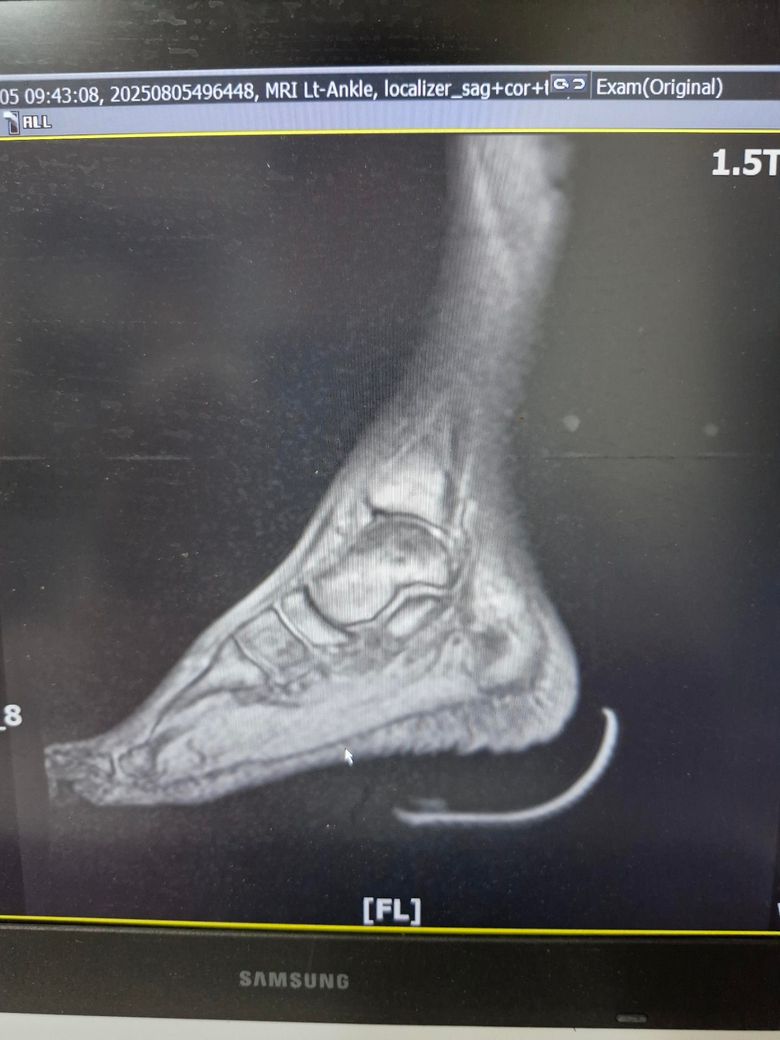

발목인대 상태 질문드립니다. (mri사진 첨부)

그래도 통증이 남아 8월 5일에 MRI를 촬영했는데, 병원에서는 “인대는 이어져 있고, 이 정도면 재활운동으로 호전될 것”이라는 설명을 들었습니다.

MRI 상 전거비인대와 발목 상태가 정말 회복 단계인지, 아니면 만성으로 넘어가는 건 아닌지 전문가분들의

의견을 듣고 싶습니다.

• 4번 째 사진

올려주신 mri를 보면 전거비인대는 연속성이 유지되고 있고 파열이나 큰 손상 흔적은 없어 재활로 회복 가능한 상태로 보입니다 다만 3개월 가까이 활동 시 통증과 미열감이 남아 있는 것은 조직 회복이 아직 완전히 끝나지 않았거나 주변 연부조직 관절 움직임 제한 등으로 인한 과민 반응일 수 있습니다.

초음파와 비교하면 mri 상으로 인대 연속성이 확인되므로 심각한 악화나 재파열은 아닌 것으로 판단됩니다